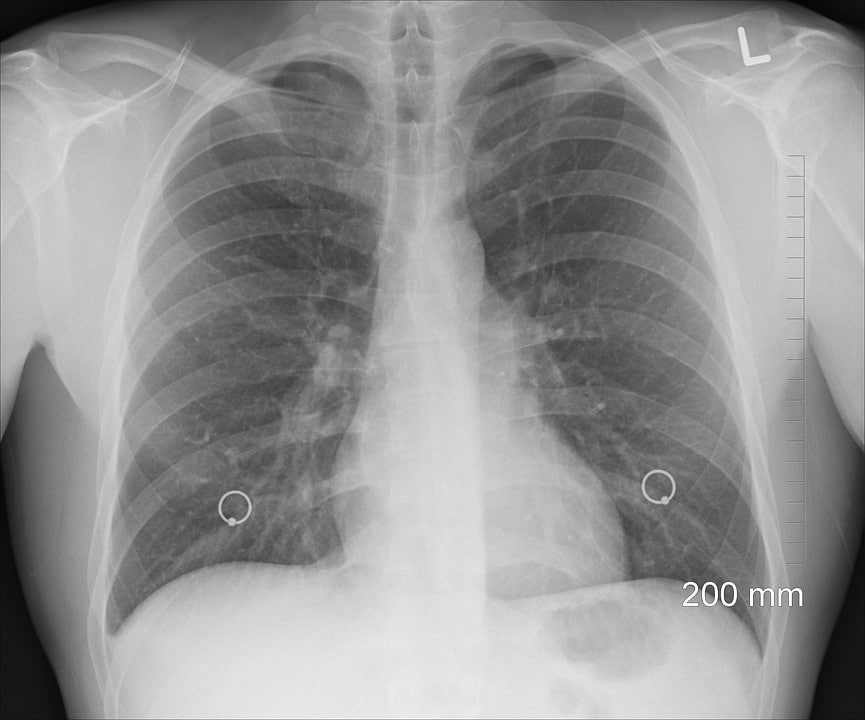

Plus les cancers sont découverts tôt, plus il est possible de sauver la personne. Le scanner obligatoire pour les fumeurs semblent donc une réponse logique à ce défi sanitaire. « Si on veut donner un chiffre simple, trois quarts des cancers du poumon sont découverts à un stade tardif actuellement ; on ne peut plus les opérer, il est trop tard (…) Quand on dépiste par scanner le chiffre est exactement inverse : trois quarts des cancers sont découverts à un stade précoce, qu’on peut opérer, et donc guérir. (…) Donc on inverse complètement la proportion par un examen qui ne fait pas mal, qui n’est pas toxique, qui est un simple scanner du thorax » plaide le professeur Charles Marquette du service pneumonologie du CHU de Nice, cité par Europe 1. D’après les calculs des spécialistes français, 7 500 vies pourraient être sauvée chaque année en France par le dépistage systématique.